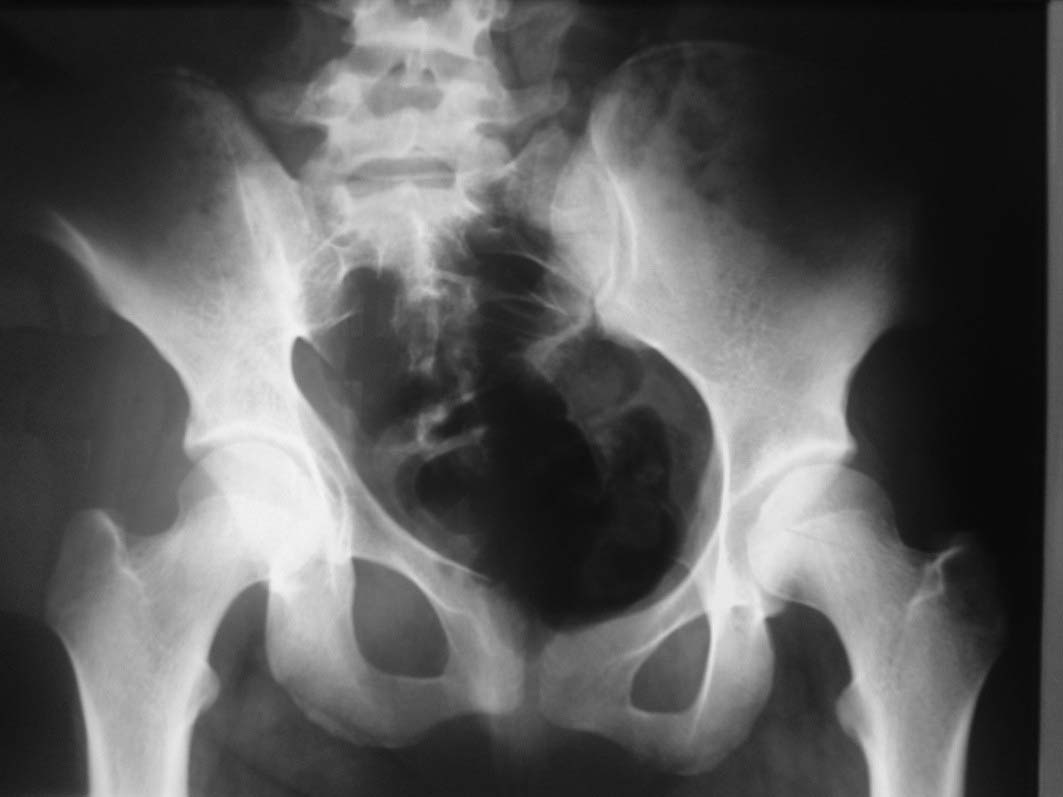

Больная 15 лет. Жалобы: на укорочение правой нижней конечности, хромоту.Анамнез: Со слов болеет с детства, травму отрицает. Ранее за медицинской помощью не обращалась. Последние 2 года отмечает резкое укорочение конечности. Локально: При осмотре отмечается умеренное искривление позвоночника во фронтальной плоскости, умеренная асимметрия лопаток и надплечий. Скошенность таза. Отмечается укорочение правой нижней конечности на 3 см. Движения в тазобедренном и коленном суставах в полном объеме. Нейрососудистых нарушений в периферических отделах нет.

Уважаемый Талгат. Просьба ответить на следующие вопросы: Укорочение у больной анатомическое или функциональное?

Как рентгенологи оценивают состояние крестцово-подвздошных сочленений, не создается ли впечатление о замыкании этого сочленения справа в предшествующие годы, а если это ощущение есть, то что привело к анкилозу этого сочленения. Нет ли по задней поверхности таза в указанной зоне рубца от имевшего место ранее свища?

Наверно целесообразно добавить,что болевого синдрома нет,движения в суставе в полном объёме.Я бы уточнил,что жалобы скорее косметического характера(асимметрия при ходьбе и западение вертельной области справа. Укорочение фигурировало как единственный диагноз в направлении на лечение к нам.Компенсация "укорочения" увеличением высоты каблука обуви не устраняет асимметрию таза и в статике и мало улучшает походку.Вопрос-стоит ли в конкретном случае идти на тройную остеотомию таза и латерализацию вертлужной впадины? Мне представляется,что не стоит.